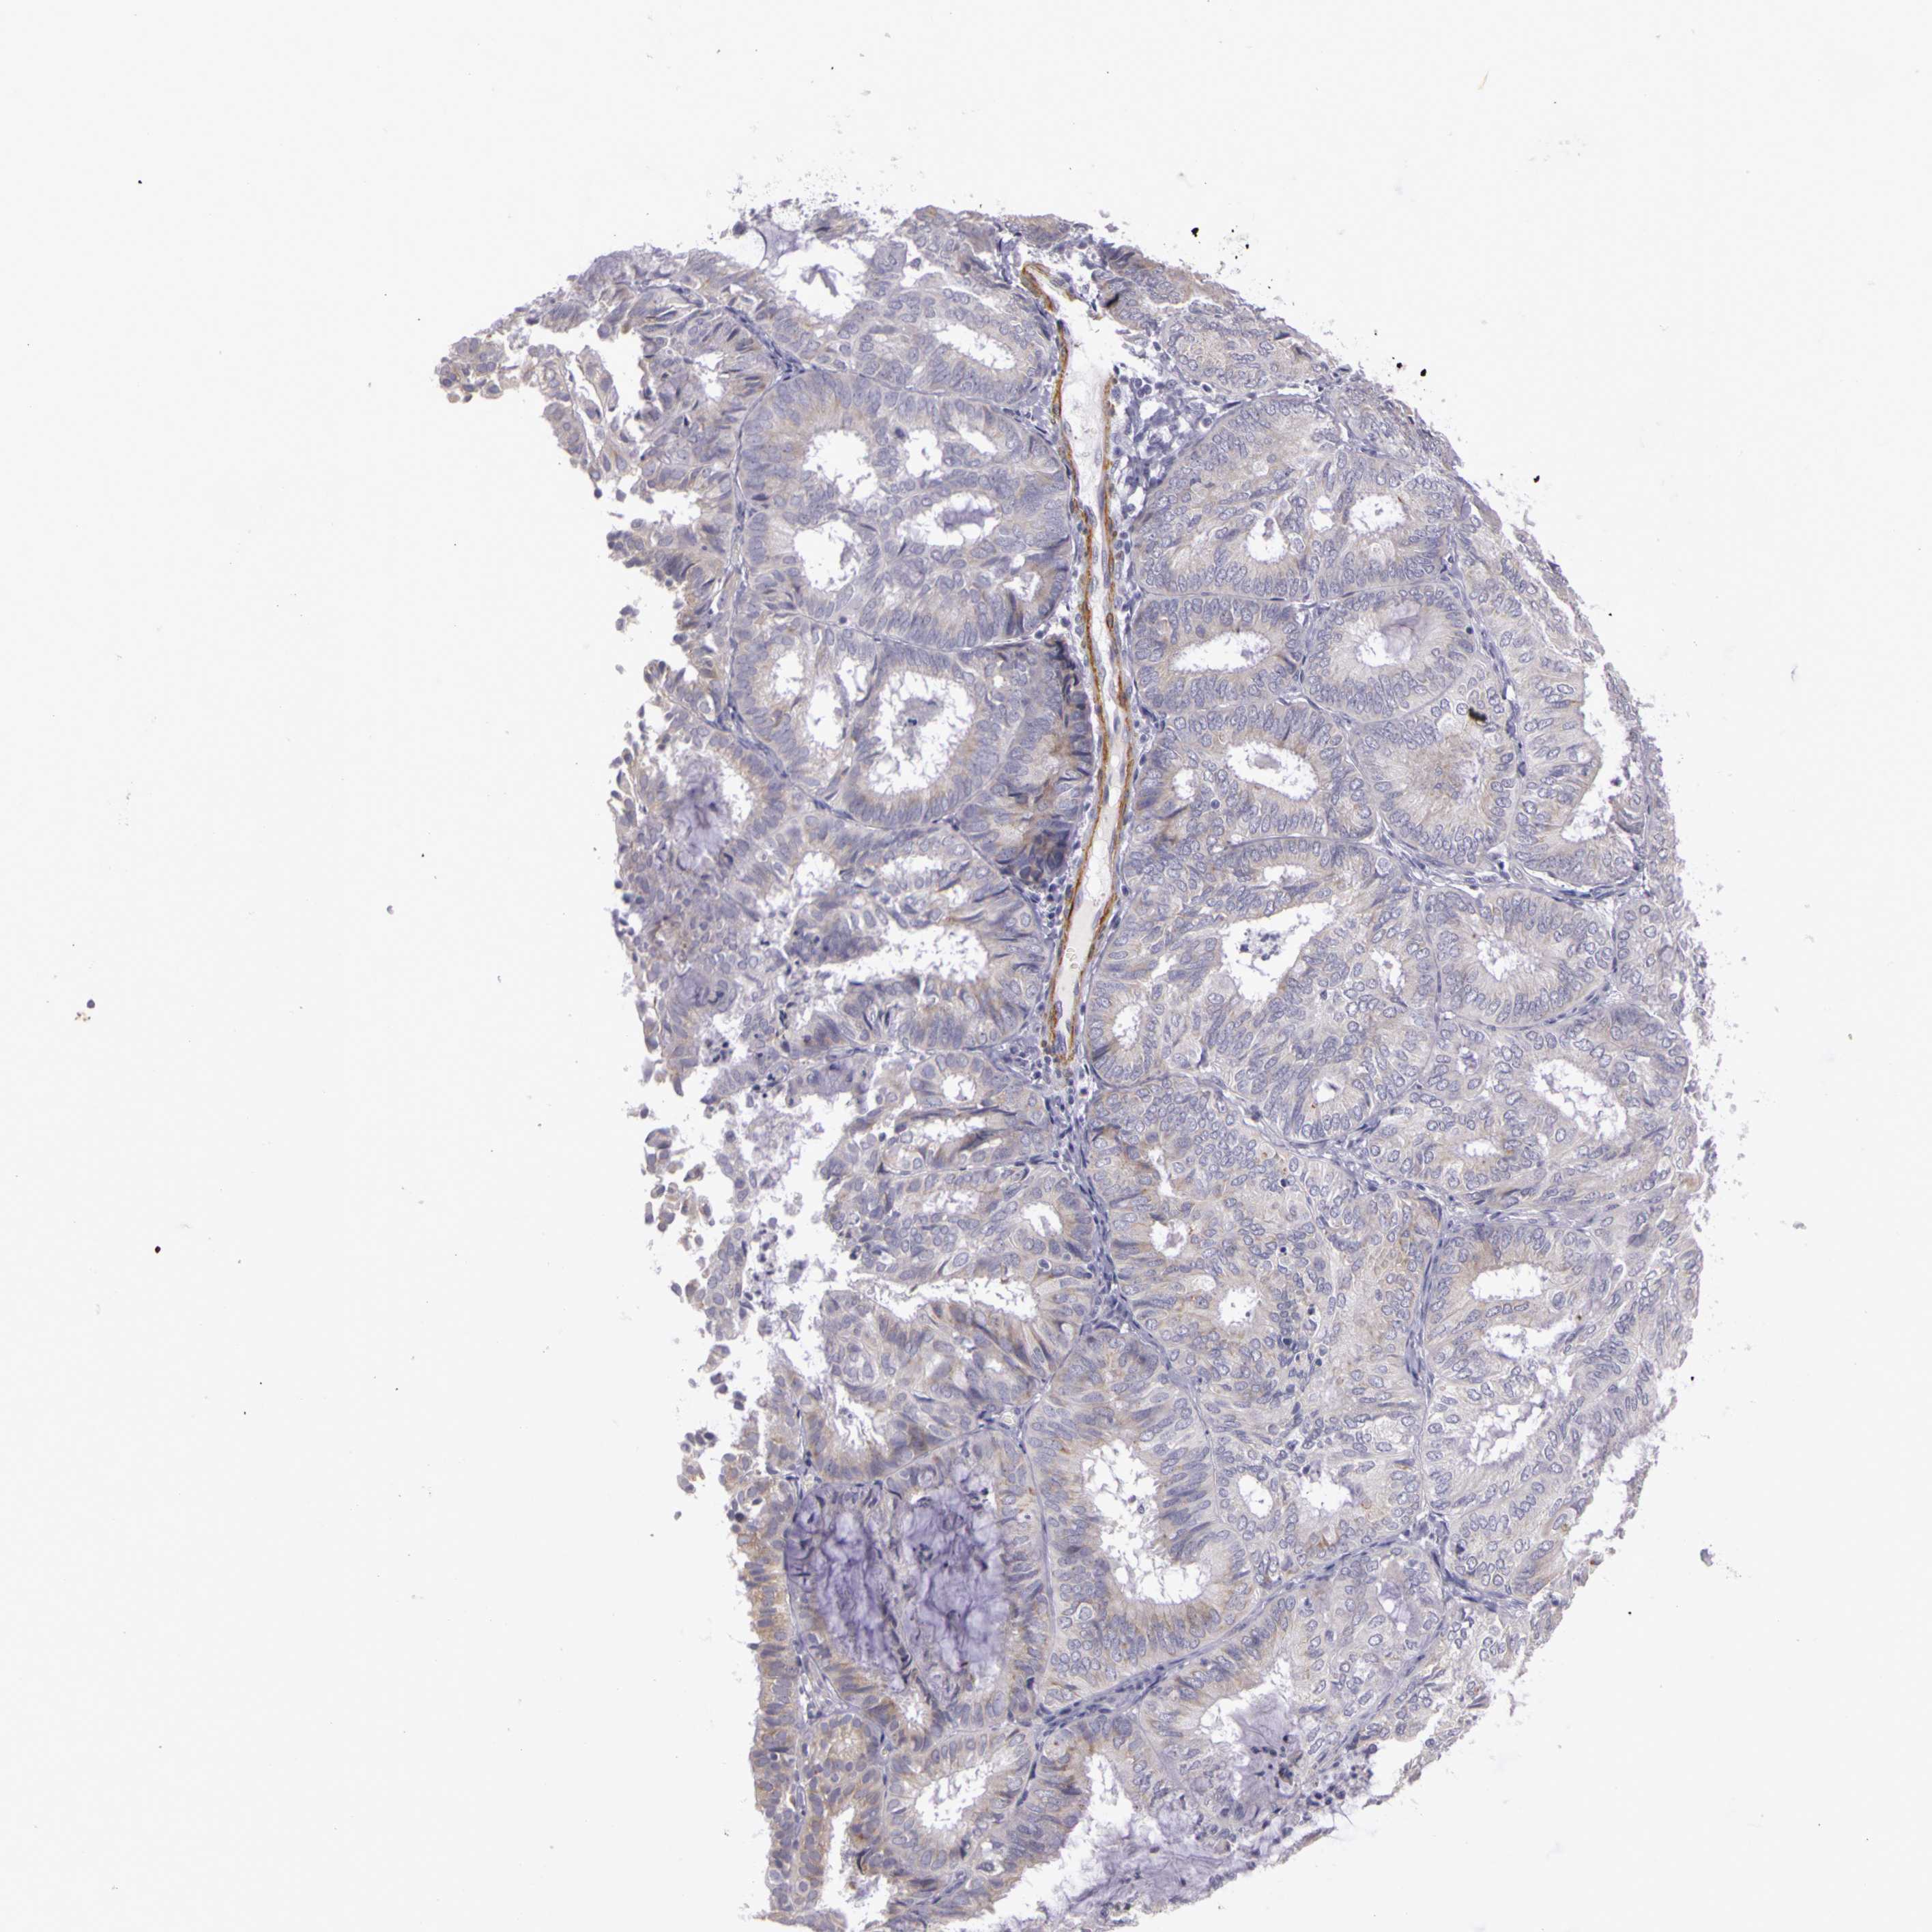

ENDOMETRIAL CANCER - Protein expressioni

A mouse-over function shows sample information and annotation data. Click on an image to view it in a full screen mode. Samples can be filtered based on level of antibody staining by selecting one or several of the following categories: high, medium, low and not detected. The assay and annotation is described here.

Note that samples used for immunohistochemistry by the Human Protein Atlas do not correspond to samples in the TCGA dataset.

Antibody stainingi

Antibody staining in the annotated cell types in the current human tissue is reported as not detected, low, medium, or high, based on conventional immunohistochemistry profiling in selected tissues. This score is based on the combination of the staining intensity and fraction of stained cells.

Each image is clickable and will lead to virtual microscopy that enables deeper exploration of all samples and also displays staining intensity scores, fraction scores and subcellular localization as well as patient and tissue information for each sample.

Antibody HPA001397

Antibody HPA012497

Staining

High

Medium

Low

Not detected

Intensity

Strong

Moderate

Weak

Negative

Quantity

>75%

75%-25%

<25%

None

Location

Nuclear

Cytoplasmic/membranous

Cytoplasmic/membranous,nuclear

Adenocarcinoma, NOS